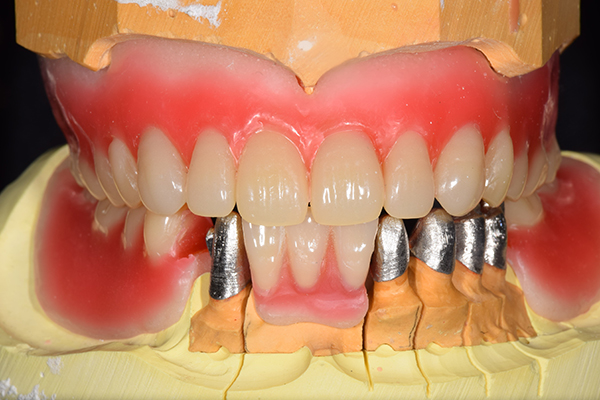

インプラント部以外にも歯周病が進行していましたので、歯周病の治療を行いました。 残念ながらインプラントと、1本の歯が残せなかったため抜歯を行いました。 その後、前歯の出っ張りを修正することと入れ歯の安定を図るため、残っている歯を全てかぶせ物にしていくことになりました。 写真中央は抜歯後に入れた治療用の入れ歯になります。 抜歯後歯ぐきが安定しましたら、入れ歯とかぶせ物の型取りを行いました。

噛み合わせチェックでしっかり奥歯で噛めるようにし、 歯を並べます。 その後、それに合わせて前歯を作っていきます。

最終的な入れ歯用の型取りをします。 シリコンで精密に型取りができました。

こちらが完成したかぶせ物と入れ歯です。かぶせ物にはアタッチメントをつけて金属のバネが見えない構造になっています。 入れ歯自体も金属を使用して、極力違和感がでないように、薄く作成しました。

お口の中に入れた状態です。 非常に見た目もよい出来となりました。 バネがみえないと見栄えが全然ちがいます。

年齢 70代・女性

主訴 奥歯のインプラントが痛い。

前歯がでてきた。

治療期間 6ヶ月

治療費 .メタルボンドクラウン7本:770,000円

.アタッチメント2個:220,000円

.義歯:550,000円

治療方針 ゆれてきたインプラントを抜去した後、歯周病の治療と、予後不良の歯を抜歯して、義歯を作成します。

抜歯後は治療用の入れ歯を作成し、ものが噛める様にします。

また前歯は、被せものをすることにしました。

治療内容 右上のボーンアンカードブリッジ(インプラントのブリッジ)部分がインプラント周囲炎になり、ぐらぐら揺れてきました。

そのため、インプラントを抜去した後、歯周病の治療と、予後不良の歯を抜歯して、義歯を作成していきました。

見た目が入れ歯とわからない様に針金のない、アタッチメントを使用した入れ歯を作成することにしました。

抜歯後は奥歯でものが噛める様に治療用の入れ歯を作成しました。

また前歯はフレアアウト(奥歯で噛めなくて前歯で噛む様になって、前歯が前に出てくる現象)していたため、患者さんの希望でかぶせ物をすることにしました。

特記事項 歯やインプラントを抜いた後は、2〜3ヶ月歯ぐきの回復を待ってから入れ歯を作るため、待機期間があります。その間、治療用の入れ歯を調整しながら使います。かぶせものをした後は歯がしみたり、場合によっては神経を抜く処置が必要になることもあります。